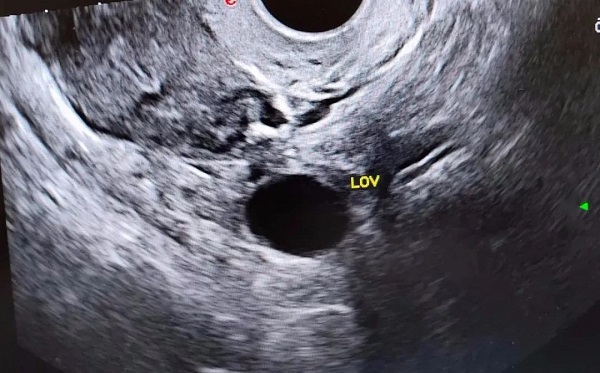

打完绒促针后仍然要做b超检测排卵情况,打针以后,有的人会出现腹水、肚子疼、卵巢过度刺激症等一些并发症,所以要密切观察有没有一些不舒服的表现。任何症状都没有的,第二天要做b超看看卵泡是否破了。

打完绒促性素后第二天要做b超看卵泡情况